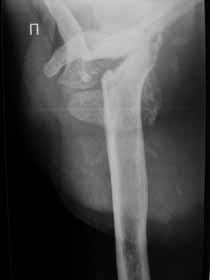

Re: Лизис костей плечевого сустава

Нужна открытая биопсия. будет саркома.

Извиняюсь, что-то фотографии сразу не прошли. сейчас исправимся.